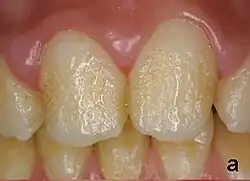

Pitting enamel hypoplasia, in an individual with amelogenesis imperfecta.

Pitting enamel hypoplasia